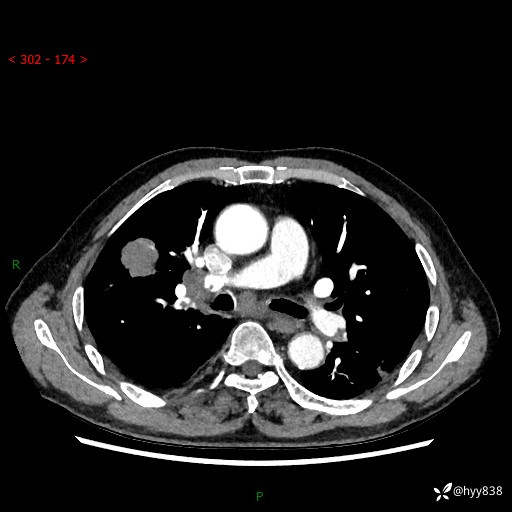

69岁/男,间断咳嗽伴气促、下肢水肿。临床拟诊肺栓,偶发肺均质强化结节--结果公布

【患者信息】:69岁/男

【主诉】:间断咳嗽伴气促、下肢水肿2周

【现病史及既往史】:患者2周来无明显诱因出现咳嗽,咳少量白痰,不易咳出,伴有气促,呈间断发作,症状与活动费力相关,以夜间为甚,不能平躺入睡,偶有憋醒,无胸闷胸痛、无发热、无头晕、头痛等不适,伴有双下肢中度水肿,就诊于当地县人民医院门诊,完善相关检查提示:左下肢深静脉血栓形成,未予以特殊处理,今患者为求进一步诊治来我院就诊,拟“心衰”收入我科。 起病以来,患者精神、饮食、睡眠可,大小便如常,体力明显下降,体重未见明显减轻。

【检查】:胸部CT增强